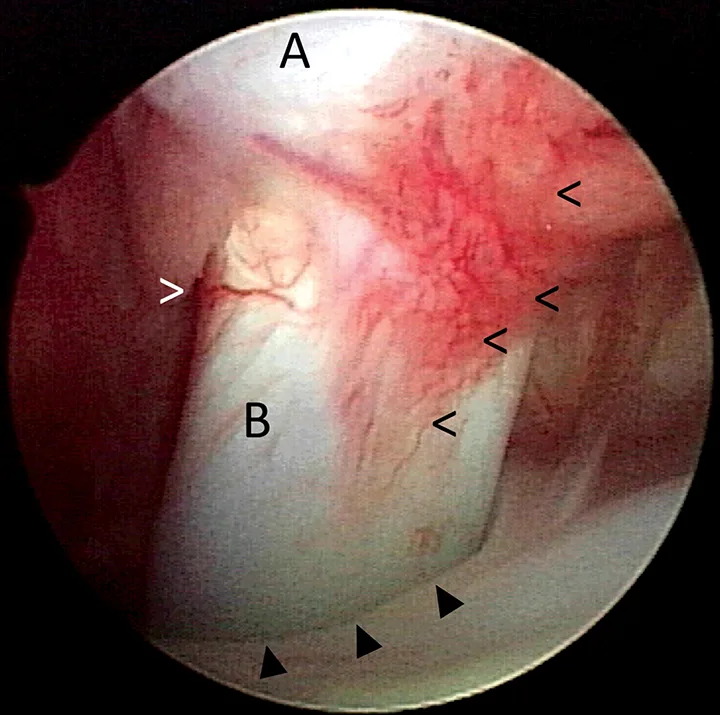

FIGURE 5

Ventrodorsal radiographic projection of a 9-year-old dog with right hindlimb lameness and hip pain. In addition to bilateral hip dysplasia and secondary osteoarthritis, mineralization is present within the right iliopsoas muscle near the tendon insertion on the lesser trochanter (arrowhead), which indicates a chronic strain injury.